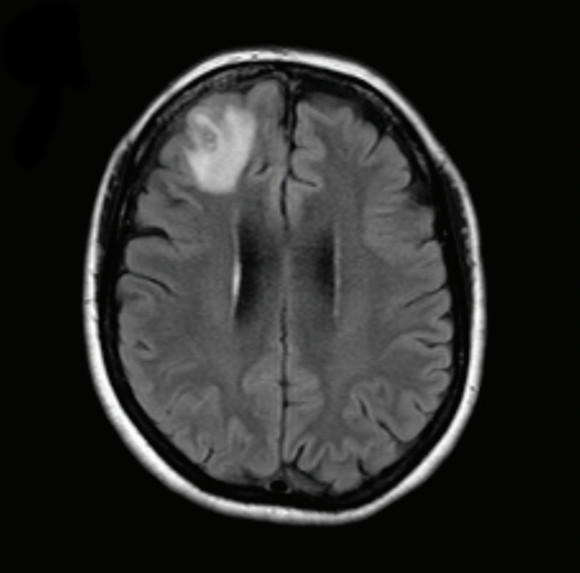

לפני כשנה וחצי, בינואר 2021, אישה בת 64 ממדינת ניו סאות’ ויילס באוסטרליה התאשפזה לאחר שסבלה במשך שלושה שבועות מכאבי בטן, שלשול, ובהמשך גם שיעול יבש והזעת לילה. לאחר כמה חודשים היא פיתחה דיכאון וקשיי זיכרון, שבעקבותיהם עברה בדיקת MRI. בבדיקה התגלה נגע במוחה, והיא נשלחה לניתוח להוצאת דגימה מהרקמה הפגועה. במהלך הניתוח הבחינה הרופאה במבנה מוזר דמוי חוט, וכששלפה אותו במלקחיים גילתה תולעת אדומה – חיה ומתפתלת – שאורכה 8 סנטימטר. בהמשך היא זוהתה כנמטודה האוסטרלית Ophidascaris robertsi, תולעת טפילית של פיתוני שטיח, שהם נחשים לא ארסיים.

בדיקת MRI של המוח מצאה נגע באוּנה המצחית הימנית. תמונה מה-MRI, עם הנגע בפינה השמאלית העליונה | מתוך המאמר, Hossain M. et al., Emerg Infect Dis. 2023